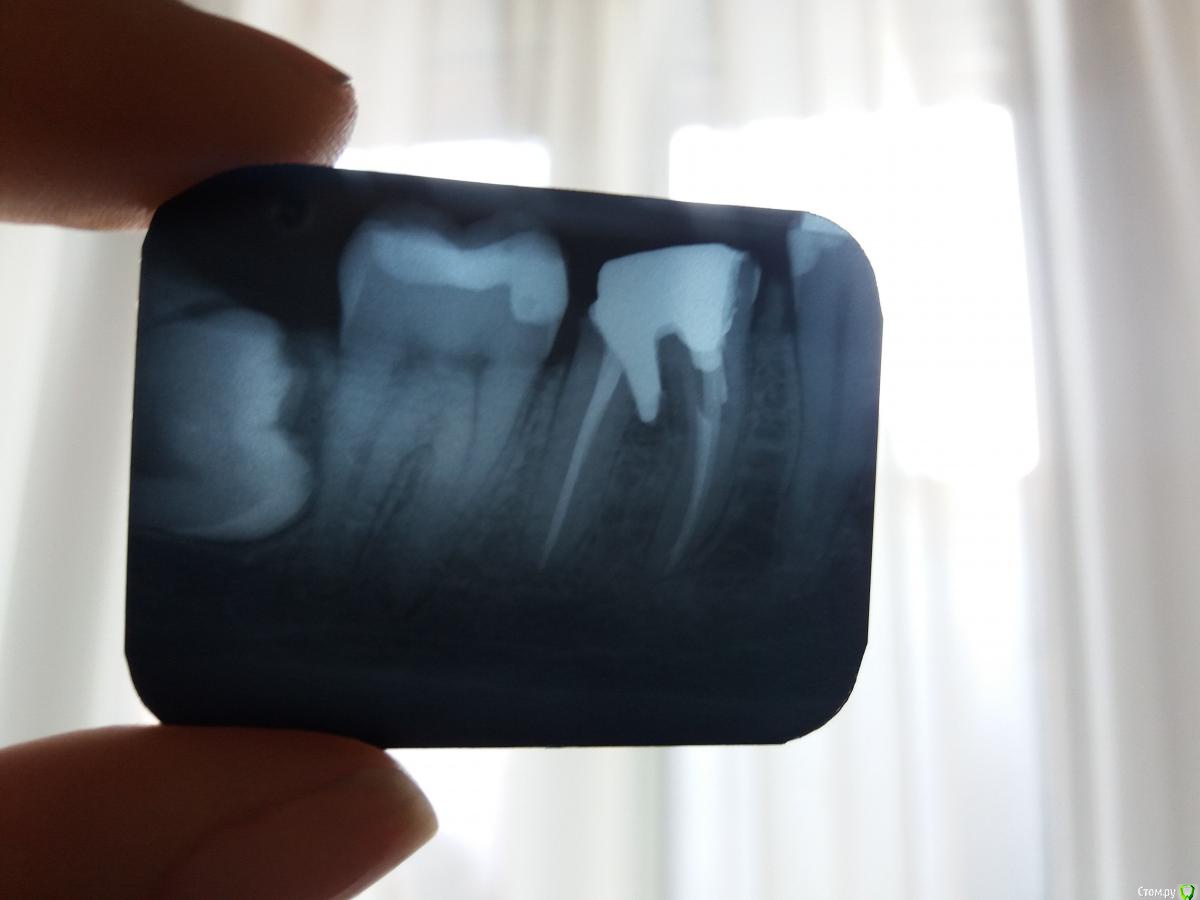

Moraine Опубликовано 19 июня, 2018 Поделиться Опубликовано 19 июня, 2018 (изменено) Здраствуйте, прошу помощи и совета специалистов, поскольку мнения розходятся. Ситуация - на снимках- первый - зуб 36 ( шестерка левая нижняя) сейчас- второй - зуб 46 ( шестерка правая нижняя) сейчас -третий - 36 на етапе подготовки под штифт После пломбирования каналов обратилась к ортодонту - ставить коронки - он мне поставил штифты металличиские ( на снимках).Потом на 36 ( левый) поставили коронку, но сразу же ( на протяжении 1,5 дня) у меня началось воспаление, пришлось коронку снять, сказал ждать 10 дней, и может надо будет зуб вырвать. Сейчас десна немного воспалены, сказал доктор полоскать содой и йодом. К правому воспросов у него нет и он меня не беспокоит, но тоже ждем ещё несколько дней , чтоб поставить коронку. Я обратилась за консультацией ещё в одну клинику, но там сказали что оба зуба надо удалить, и что шрифты установлены неверно. С их слов, спасти зубы шансов нет, из-за действий с штифтом, теперь только импланты. Я теперь не знаю, что думать. Выходит, что мне испортили зубы. на коротые при грамотном подходе можно было поставить коронки? Или в другой клинике очень радикально подходят к вопросу? Прошу озвучить Вашее профессиональное мнение - действительно ли критически неверно установлен штифт и какие шансы спасти зубы? А также какие риски при установленни коронки на 46? Благодарю заранее за помощь. Изменено 19 июня, 2018 пользователем Moraine Ссылка на комментарий

chervoncevdaniil Опубликовано 19 июня, 2018 Поделиться Опубликовано 19 июня, 2018 К сожалению,оба на удаление 6 Ссылка на комментарий

red_butler Опубликовано 19 июня, 2018 Поделиться Опубликовано 19 июня, 2018 К сожалению,оба на удаление +1 1 Ссылка на комментарий

Дмитрий Л. Опубликовано 19 июня, 2018 Поделиться Опубликовано 19 июня, 2018 +1 но если как можно быстрее удалить штифты и запломбировать дно зуба то есть небольшой шанс спасти. Правда вменяемый врач пойдёт по этому пути если вы четко поймёте что такое лечение может быть безуспешным и возьмёте ответственность на себя. Выжидательная тактика или полоскания себя не оправдают. 1 Ссылка на комментарий